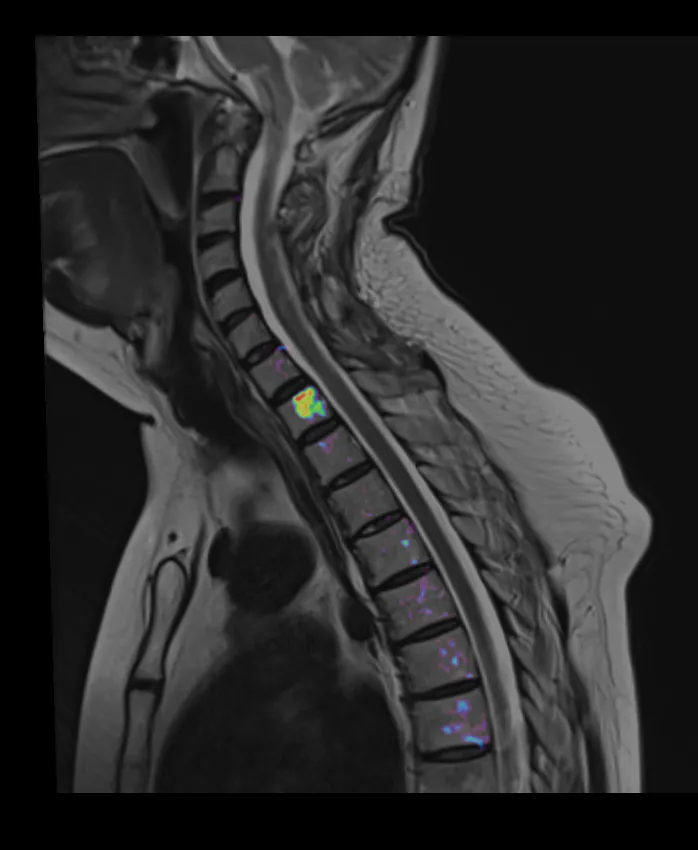

МРТ-онкоскрининг позвоночника

МРТ позвоночника (скрининг mts)

✔️Технология "Псевдо-ПЭТ" используется для диагностики метастатических поражений, лимфом.